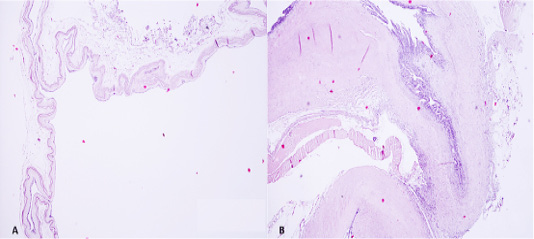

In A swim bladder torsion, the point (arrow) where the torsion happened, and in B a normal swim bladder (anterior chamber -AC, posterior chamber -PC, communicating duct -CD and pneumatic duct -PD). On the left a schematic representation of the torsion (A) and normal swim bladder (B).

Anterior chamber presented a single layer of flattened epithelial cells, with a prominent basal lamina below the epithelial cells and lamina propria containing collagen fibrils, elastic fibres, and fibroblasts. In B section in the point where the torsion occurred. Many cells were degraded due to the rapid decomposition of the corpse (H&E, 40x).